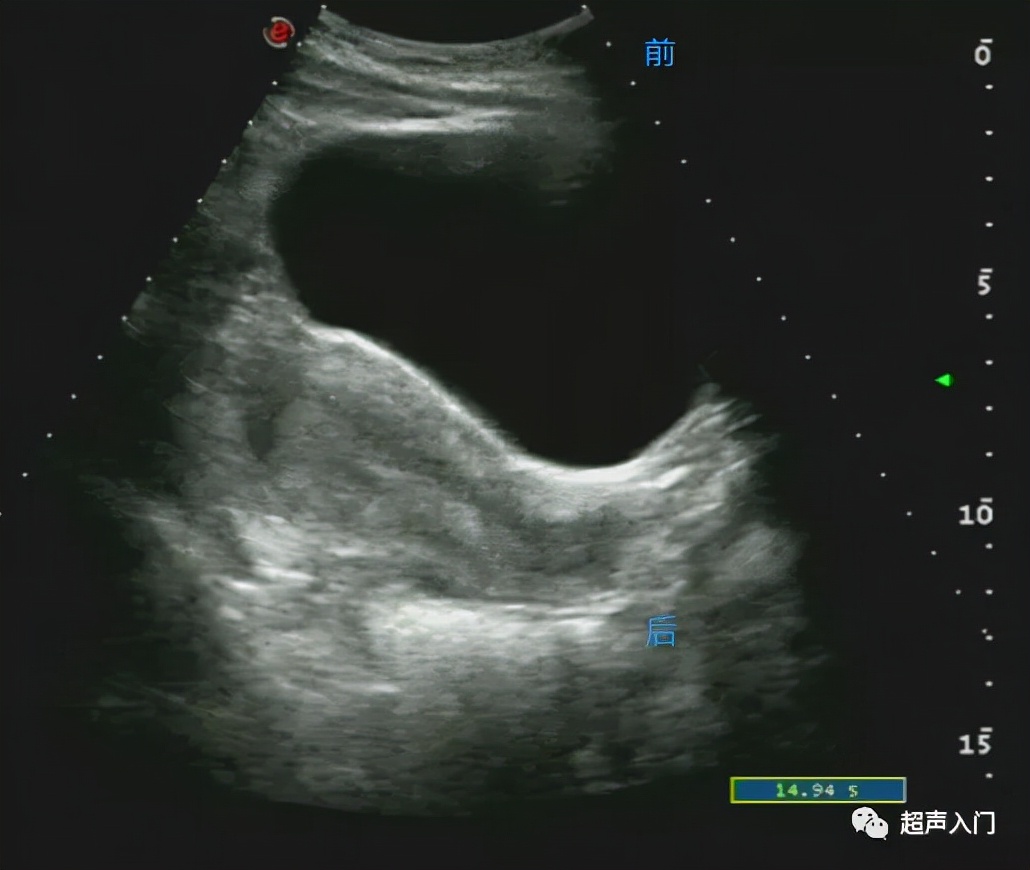

首先我们一起来了解经腹部超声看子宫如何区分前后。当宫体向前(腹壁侧)倾向的时候,我们就说此刻子宫为前位,同理,靠前方的子宫壁,也就称为前壁,子宫壁距离人体背侧近的时候为后壁。

所以经腹部看的超声不管是前平后位子宫,靠近腹侧的子宫壁就称为前壁。

描述清楚子宫壁是为了更好的定位肿瘤、肌瘤或子宫实质病变,给临床提供准确的信息。